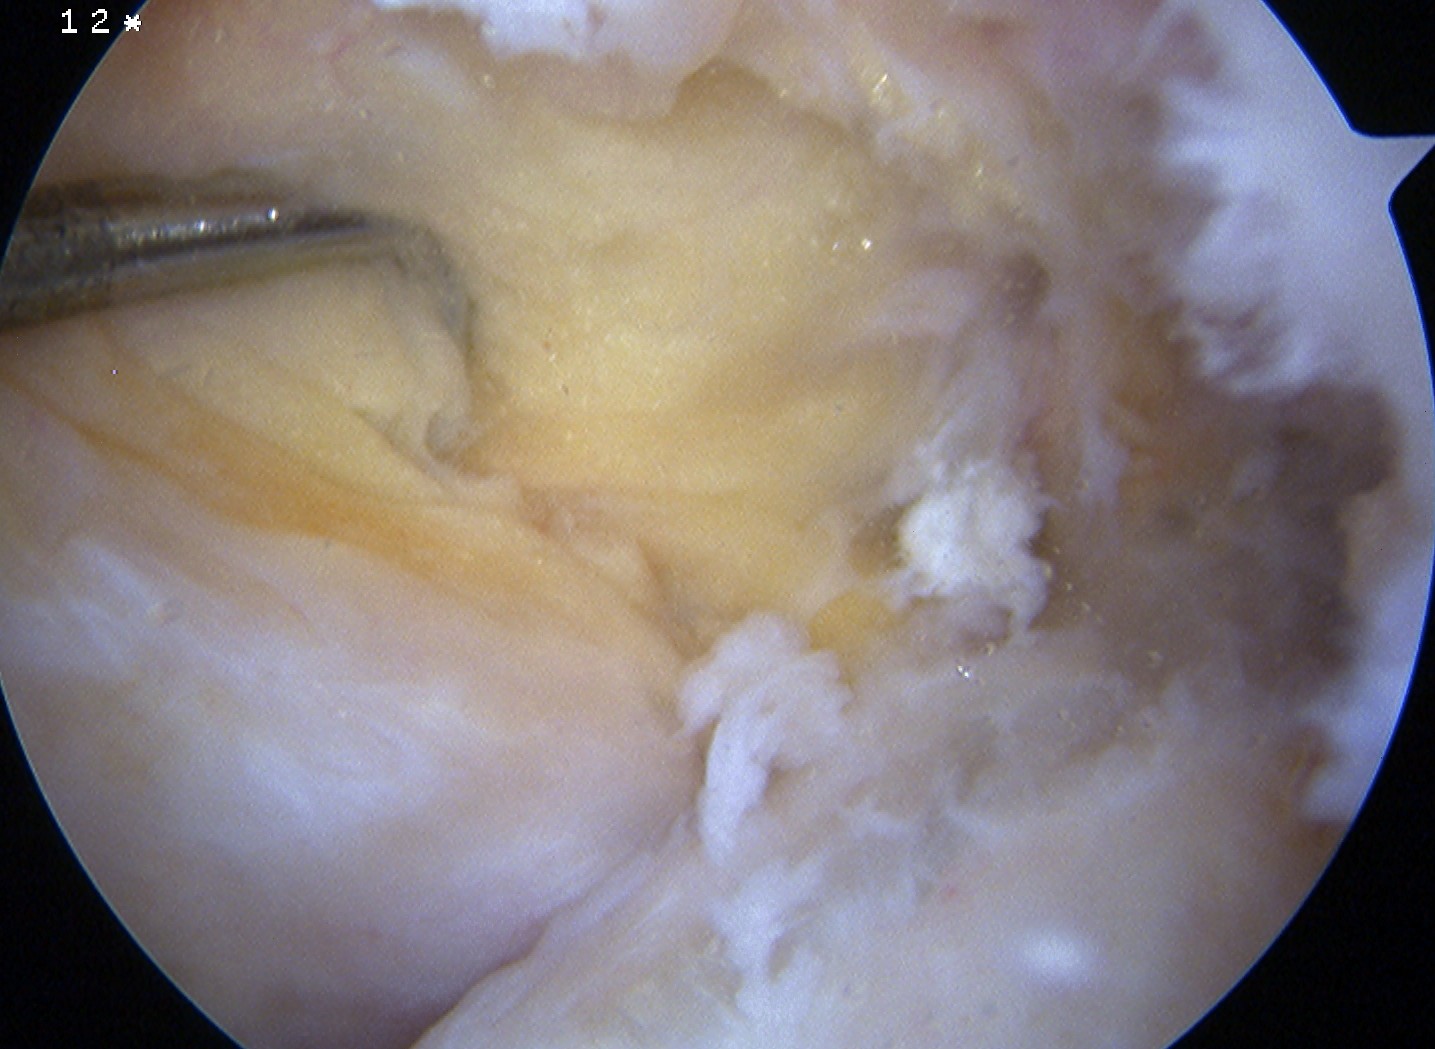

Arthroscopy

May miss tear as is extra-synovial

Chronic PCL tear from femur

Acute PCL femoral avulsion